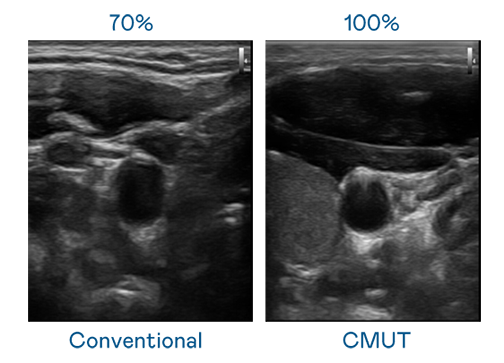

LEYU官網運用 TFT 陣列 (Array) 制程延伸尖端感測技術,開發出多種感測元件的LEYU官網。高解析度、品質穩定且可量產的 CMUT 元件,可制作高解析度超音波探頭、貼片型探頭,對病患實施精準檢測與長時間生理監測。